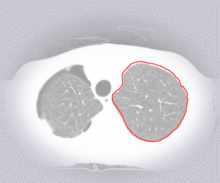

Ballooning Snake

2-D Edge Detection

Segmentation with

Greedy Algorithm